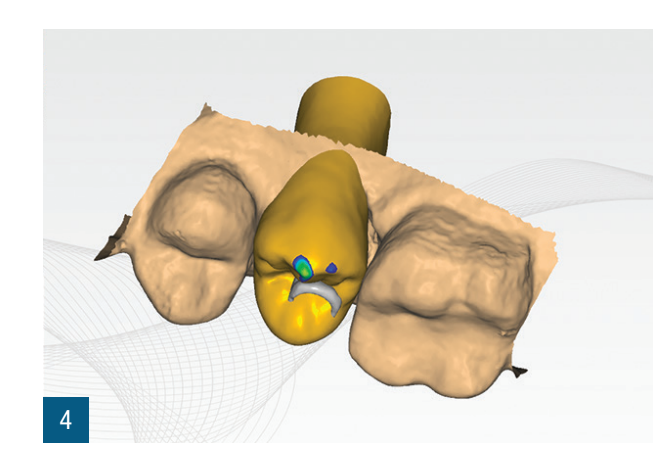

Пацієнтка 36 років звернулася до нас з частковим переломом коронки другого премоляра праворуч (1.5). Після перевірки неможливості консервативного відновлення було заплановано імплантно-протезне лікування з негайною екстракцією для заміни ураженого елемента (Рис. 1,2). Пацієнтка, не курець, була класифікована як ASA 1. Було виконано локалізовану CBCT в ураженій області для перевірки наявності та морфології вестибулярної кісткової стінки навколо елемента, що підлягає екстракції, в альвеолярному відростку. Перед екстракцією 1.5 була виконана цифрова внутрішньоротова відбитка (iTero Flex, Align Technology) зуба та прилеглих ділянок (Рис. 3). Після плескальної анестезії була виконана екстракція, обмежуючи травму пародонтальних тканин, розділяючи корені та використовуючи міні-важелі та синдесмотоми для збереження вестибулярної кісткової пластини. Оцінюючи цілісність альвеоли та сприятливі анатомічні умови, переходять до встановлення імплантату розмірів, що забезпечують адекватну первинну стабільність (4.1 x 11,5 TSVH ZimmerBiomet). Імплантат розміщується в близькій до піднебіння позиції відповідно до вказівок літератури (Рис. 6,7), заповнюючи проміжок між імплантатом та вестибулярною кістковою кортикою за допомогою гетерологічної кісткової пересадки (Copioss Zimmer-Biomet). Монтажний пристрій формують так, ніби це абатмент, і після його закручування на імплантаті проводять сканування. З цифрового внутрішньоротового сканування виконується CAD проектування гвинта загоєння (Рис. 4). У проекті буде використано як передекстраційне сканування, так і сканування з монтажним пристроєм, перетвореним в абатмент, щоб максимально точно відтворити гвинт загоєння. Морфологія гвинта загоєння відтворить існуючі тканинні умови на момент хірургії та дозволить уникнути естетичних дефектів у рожевій естетиці. Завершивши цифрове проектування, виконується 3D-друк з смоли (Lab2 Formlab) кастомізованого гвинта загоєння. Після завершення друку, отриманий гвинт загоєння з смоли Nextdent цементується з авто- та фото-твердим смолистим цементом (Relix Unicem, 3M) до абатмента, отриманого з монтажного пристрою, а потім закручується на імплантат (Рис. 5,6). Було проведено рентгенологічні контролі через три місяці та через рік (Рис. 7,8). Через 3 місяці була виготовлена остаточна коронка через цифровий потік з тим самим сканером та спеціальними сканбоді (Gentek, Zfx), які дозволяють ідентифікувати точне просторове положення імплантату. Через тиждень була передана остаточна монолітна коронка з фарбованої цирконії, закручена на ti-base (Рис. 9,10). Через рік було виконано ще одне сканування для оцінки з часом можливих об'ємних змін періімплантних тканин. Сканування, виконані на етапі передекстракції та через рік, були оброблені за допомогою спеціалізованого програмного забезпечення (meshlab) для оцінки розмірних змін (Рис.11-13).